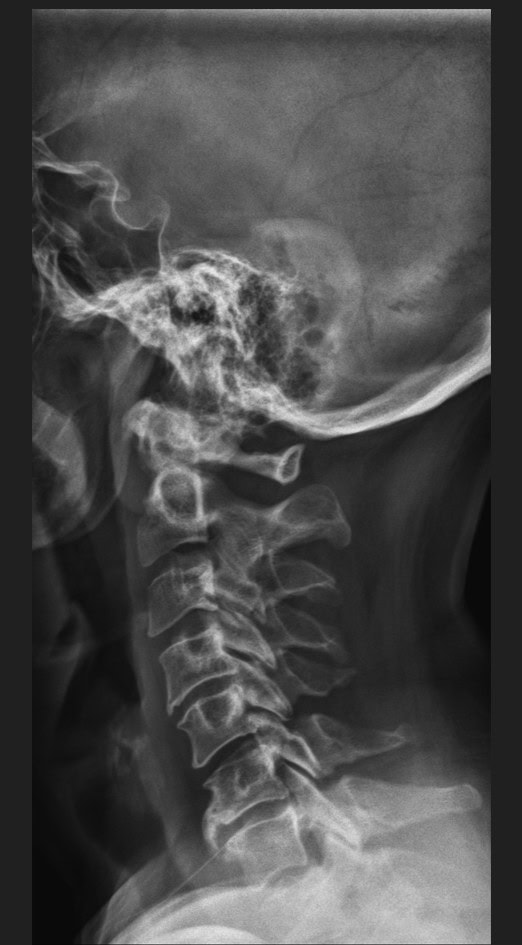

Pre Scan